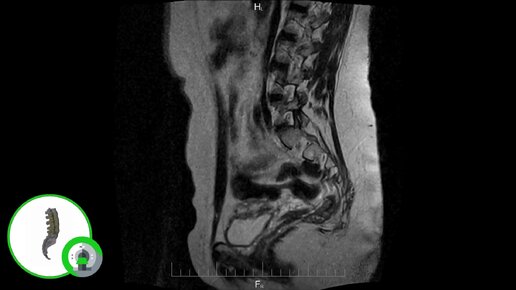

Что покажет МРТ копчика (видео)